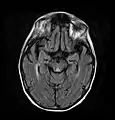

Brain atrophy associated with WKS occurs in the following regions of the brain:

1. the mammillary bodies,

2. the thalamus,

3. the periaqueductal grey,

4. the walls of the 3rd ventricle,

5. the floor of the 4th ventricle,

6. the cerebellum, and

7. the frontal lobe.

In addition to the damage seen in these areas there have been reports of damage to cortex, although it was noted that this may be due to the direct toxic effects of alcohol as opposed to thiamine deficiency that has been attributed as the underlying cause of Wernicke-Korsakoff Syndrome.[25]

The amnesia that is associated with this syndrome is a result of the atrophy in the structures of the diencephalon (the thalamus, hypothalamus and mammillary bodies), and is similar to amnesia that is presented as a result of other cases of damage to the medial temporal lobe.[26] It has been argued that the memory impairments can occur as a result of damage along any part of the mammillo-thalamic tract, which explains how WKS can develop in patients with damage exclusively to either the thalamus or the mammillary bodies.[25]

Frequently, secondary to thiamine deficiency and subsequent cytotoxic edema in Wernicke encephalopathy, patients will have marked degeneration of the mammillary bodies. Thiamine (vitamin B1) is an essential coenzyme in carbohydrate metabolism and is also a regulator of osmotic gradient. Its deficiency may cause swelling of the intracellular space and local disruption of the blood-brain barrier. Brain tissue is very sensitive to changes in electrolytes and pressure and edema can be cytotoxic. In Wernicke this occurs specifically in the mammillary bodies, medial thalami, tectal plate, and periaqueductal areas. People with the condition may also exhibit a dislike for sunlight and so may wish to stay indoors with the lights off. The mechanism of this degeneration is unknown, but it supports the current neurological theory that the mammillary bodies play a role in various "memory circuits" within the brain. An example of a memory circuit is the Papez circuit.